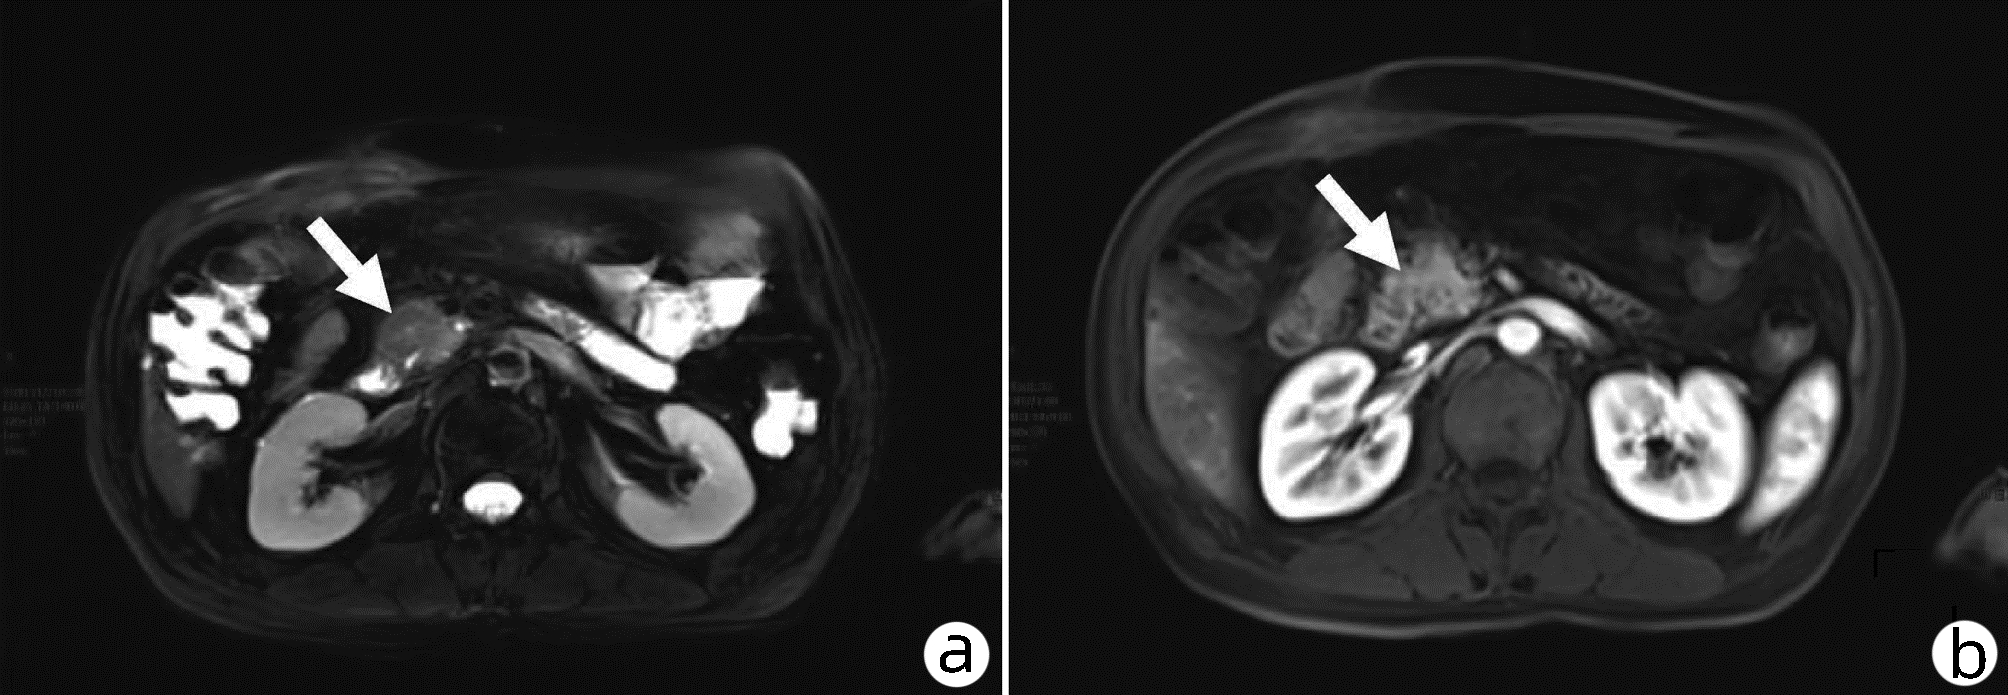

Efficacy of magnetic resonance IDEAL-IQ technique in diagnosis of fat and iron deposition in acute pancreatitis

Huifang FAN, Qiang CHEN, Xiaojun YUAN, Lin LUO

2022, 38(10): 2320-2324. DOI: 10.3969/j.issn.1001-5256.2022.10.022

Abstract(1240) HTML (498) PDF (2190KB)(69)

Abstract:

Objective  To perform quantitative evaluation of fat and iron deposition in the pancreas of patients with acute pancreatitis (AP) based on the IDEAL-IQ quantitative parameters fat fraction (FF) and relaxation rate (R2*), and to investigate the efficacy of this technique in the diagnosis of AP.  Methods  A total of 72 patients with AP who were diagnosed and treated in The First Affiliated Hospital of Baotou Medical College, Inner Mongolia University of Science and Technology from October 2020 to October 2021, were enrolled as case group, and 82 healthy controls who underwent physical examination during the same period of time were enrolled as control group. The abdominal IDEAL-IQ sequence test was performed for both groups using GE 3.0T magnetic resonance instrument, and FF and R2* values were measured on post-processing workstation. The t-test was used for comparison of normally distributed continuous data between groups, and the Mann-Whitney U test was used for comparison of non-normally distributed continuous data between groups. A receiver operating characteristic (ROC) curve analysis was performed for the parameters with statistical significance, and area under the ROC curve (AUC) was used to evaluate the diagnostic efficacy of parameters.  Results  Compared with the control group, the case group had significantly higher FF value (Z=-10.01, P < 0.001) and R2* value (Z=-3.73, P < 0.001), while there were no significant differences in FF and R2* values between mild AP and moderate-to-severe AP (P > 0.05). FF value had a sensitivity of 100% and a specificity of 90.2% in the diagnosis of AP, while R2* value had a sensitivity of 48.6% and a specificity of 86.6% in the diagnosis of AP.  Conclusion  The quantitative parameter FF value of magnetic resonance IDEAL-IQ technique has relatively high sensitivity and specificity in the diagnosis of AP, and it is a specific index for the diagnosis of AP and holds promise for clinical application.